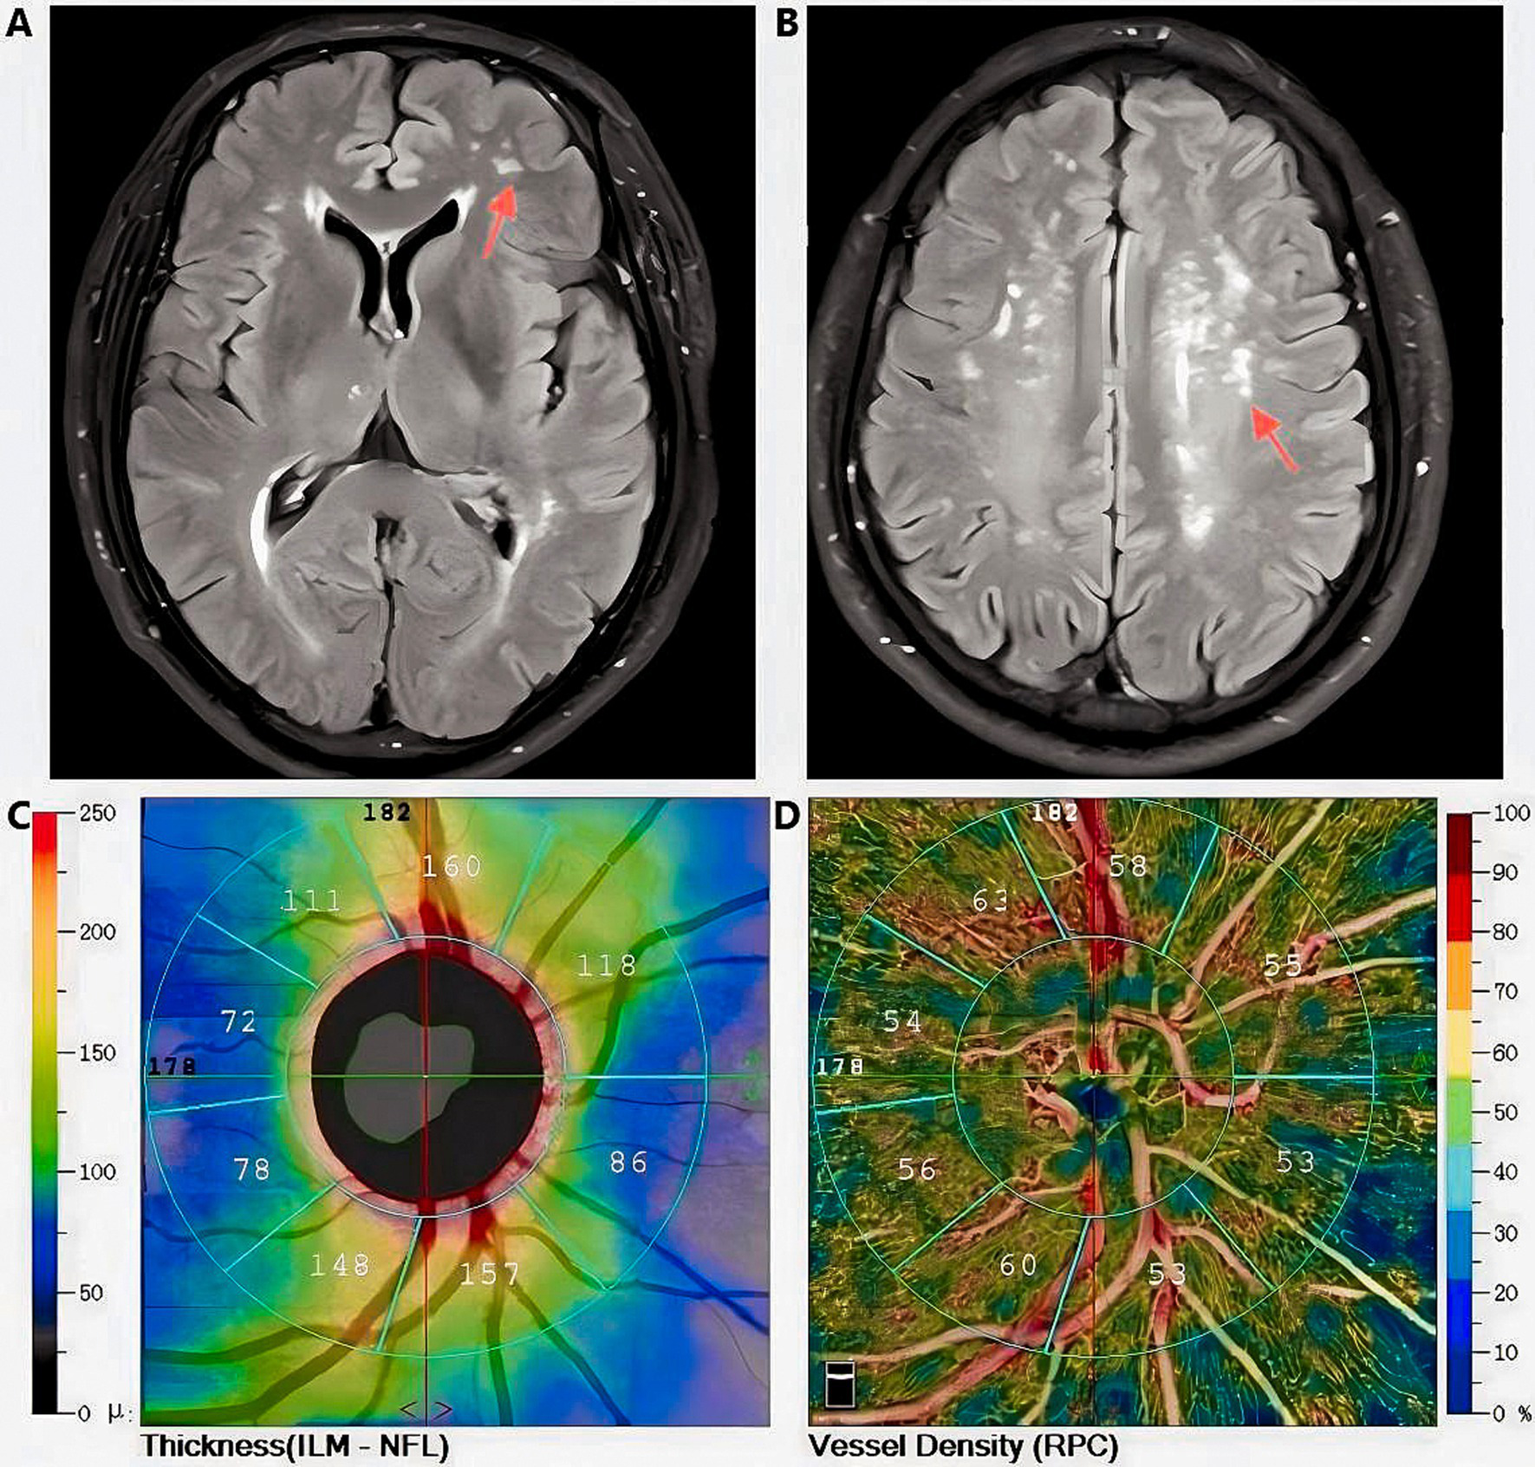

This observational study systematically examined the relation between the extent of WMLs involvement and various retinal parameters, including ILM-IPL thickness, SCP and DCP vessel density, RNFL thickness, and FAZ area (Figure 5). The results showed that the degree of WMLs was significantly associated with various indicators of OCTA. As the white matter lesions progressively deteriorate, the vessel density and retinal thickness in all quadrants of the retina also decreased. Simultaneously, the FAZ region is progressively expanding. In other words, as the severity of white matter lesions increases, patients exhibit a thinner retinal thickness, reduced vascular density, and a larger extent of ischemia compared to healthy individuals.

Figure 5

Magnetic Resonance Imaging T2-FLAIR characteristic images of white matter lesions (indicated by the red arrow) in a Fazekas grade 2 subject, along with retinal thickness and vascular density data obtained via Optical Coherence Tomography Angiography (Images from the same subject); A, B: Diagram of white matter lesions; C: Retinal thickness measurement diagram; D:Diagram of vascular density measurement.